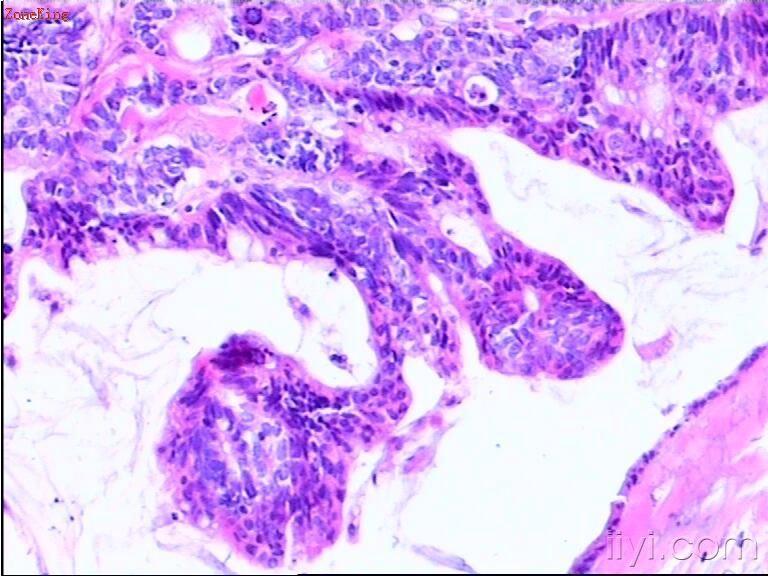

睾丸肿物,30岁,肿物位于睾丸白膜内,紧靠白膜,切面呈胶冻状。

部分区被覆上皮为粘液性上皮,考虑为粘液性囊腺癌;

30岁男子,睾丸肿块,有以下考虑:1. NSGCT2. 睾丸类癌。可以作为NSGCT的一个成分,也可以是来源于自身内分泌细胞的一个原发肿瘤或者是来自胃肠道肿瘤的一个转移瘤。 建议进一步做相关免疫组化(PLAP、AFP、HPL、NSE、PSA、β-HCG、CD30、EMA等待)或全面检查确诊。